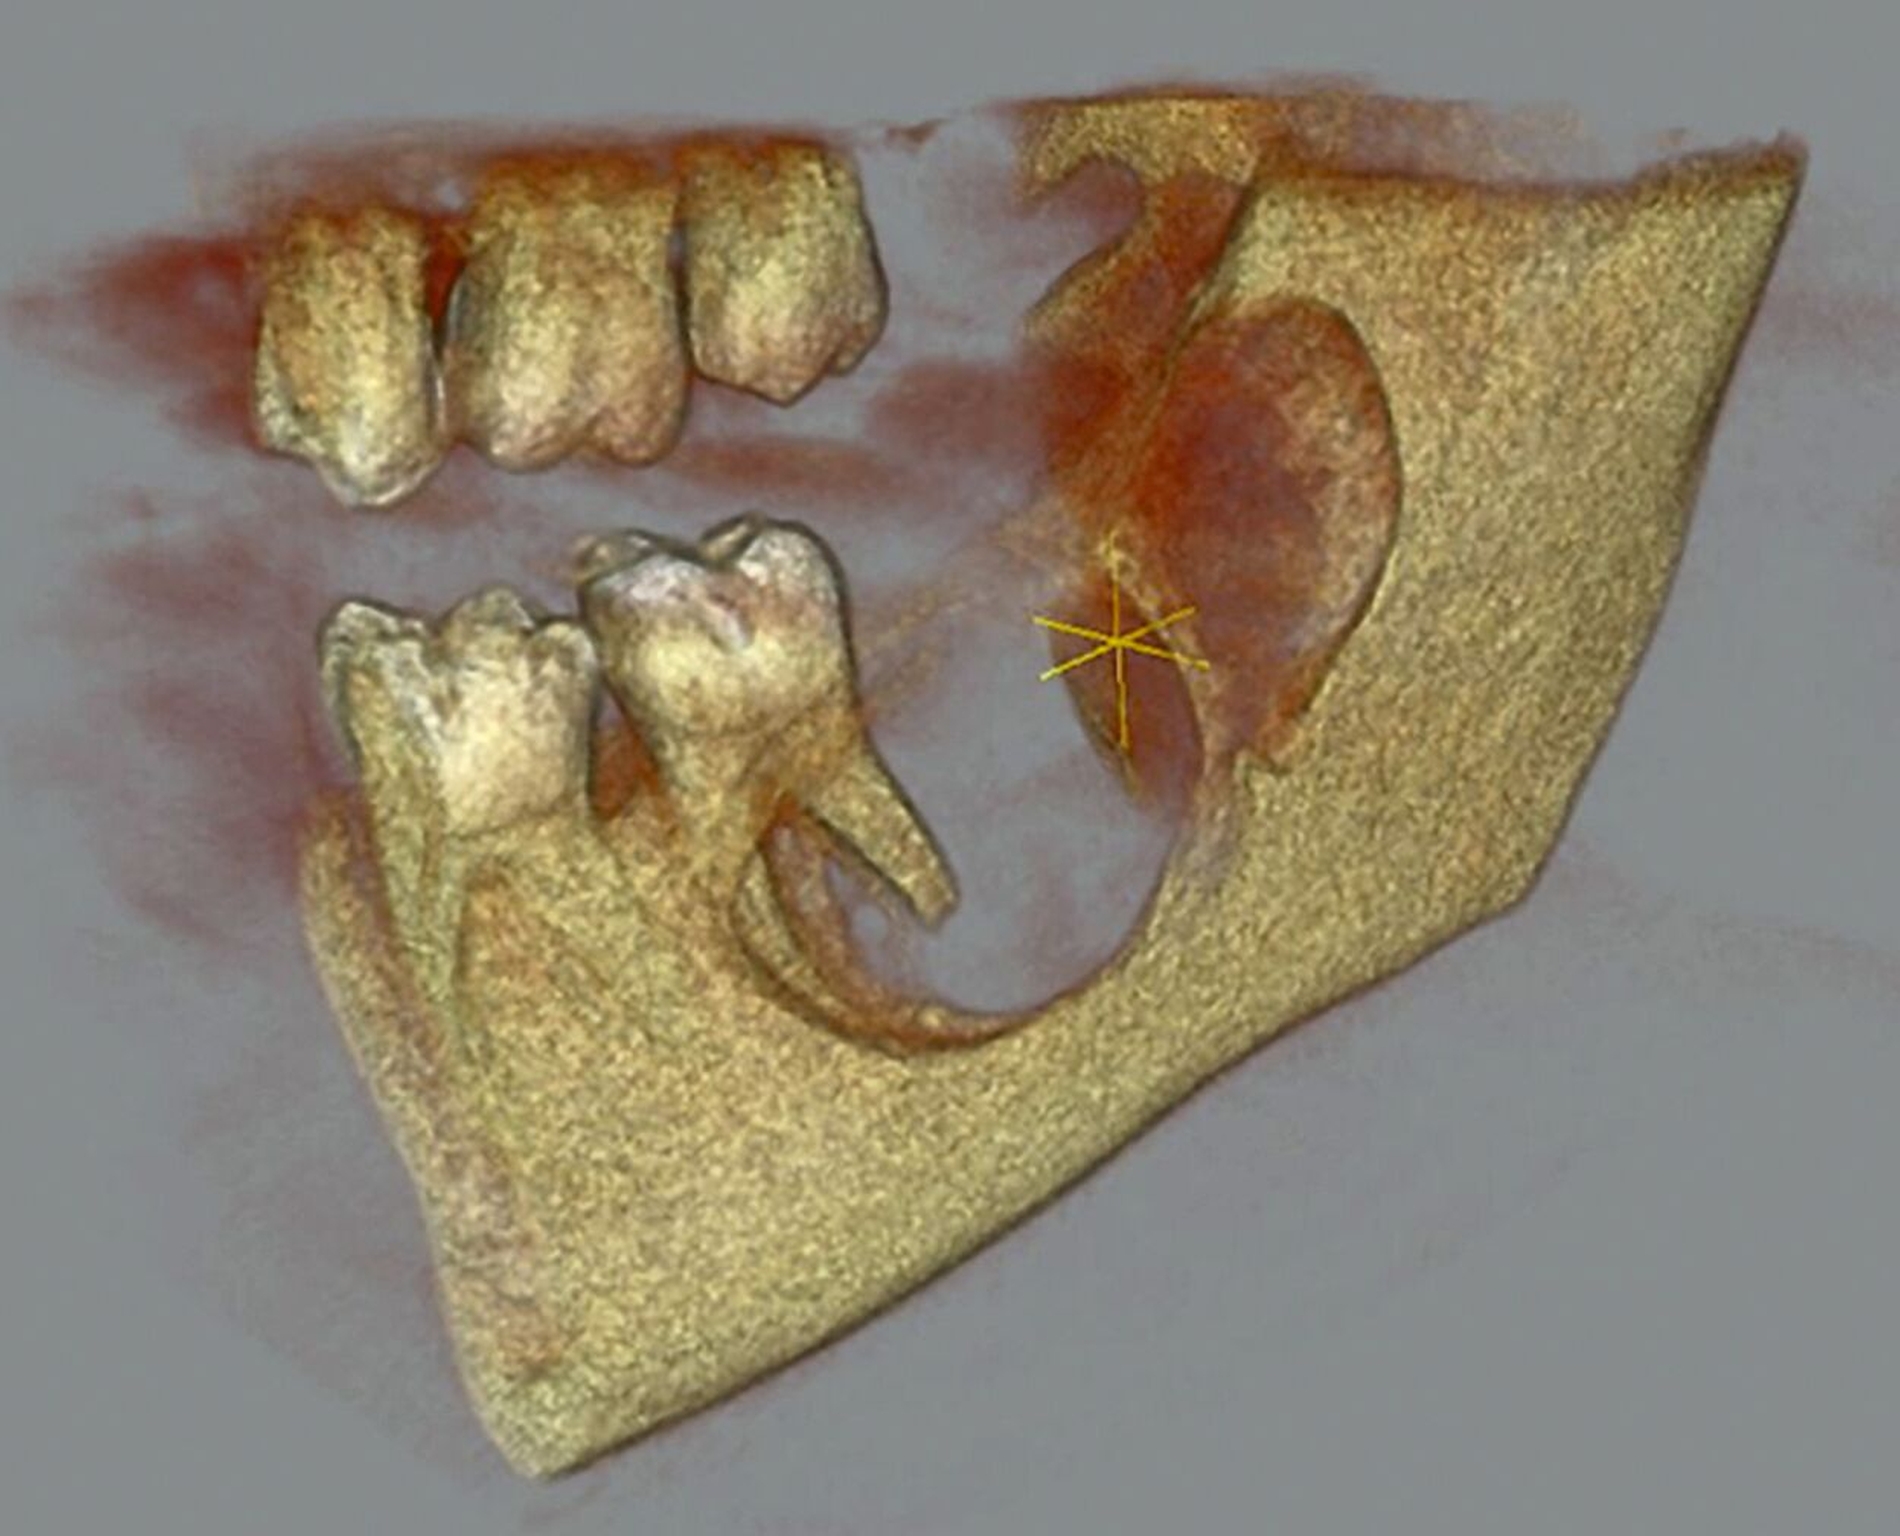

Die digitale Volumentomografie (DVT) ergab eine mehrkammerige, radioluzente Raumforderung, die sich bei erhaltener Kortikalis von der mesialen Wurzel des Zahnes 37 bis in den aufsteigenden Ast des Ramus mandibulae erstreckte (Abbildungen 1 und 2). Aufgrund der Morphologie bestand der Verdacht auf einen keratozystischen odontogenen Tumor, differenzialdiagnostisch auf andere odontogene Tumoren. Nach Aufklärung wurden die Extraktion des nicht erhaltungswürdigen Zahnes 37 sowie die Zystektomie geplant und zwei Wochen später in Intubationsnarkose durchgeführt.

Operativ erfolgte eine krestale Inzision mit marginaler Fortführung und vestibulärer Entlastung. Vestibulär fand sich eine papierdünne Knochenlamelle, die den zystischen Hohlraum noch bedeckte (Abbildung 3a). Der Zahn 37 wurde gemeinsam mit dem Zystenbalg en bloc entfernt. Anschließend wurden die Zystenwände unter Schonung des N. alveolaris inferior im Sinne einer erweiterten Zystektomie ausgefräst (Abbildung 3b).

Der Wundverschluss erfolgte spannungsfrei (Abbildung 3c). Das Präparat mit dem extrahierten Zahn 37 und anhaftendem Zystenbalg ist in Abbildung 4 dokumentiert. Die Histopathologie ergab ein bis 1,8 cm messendes Ameloblastom; molekularpathologisch wurde eine BRAF-V600E-Mutation nachgewiesen.